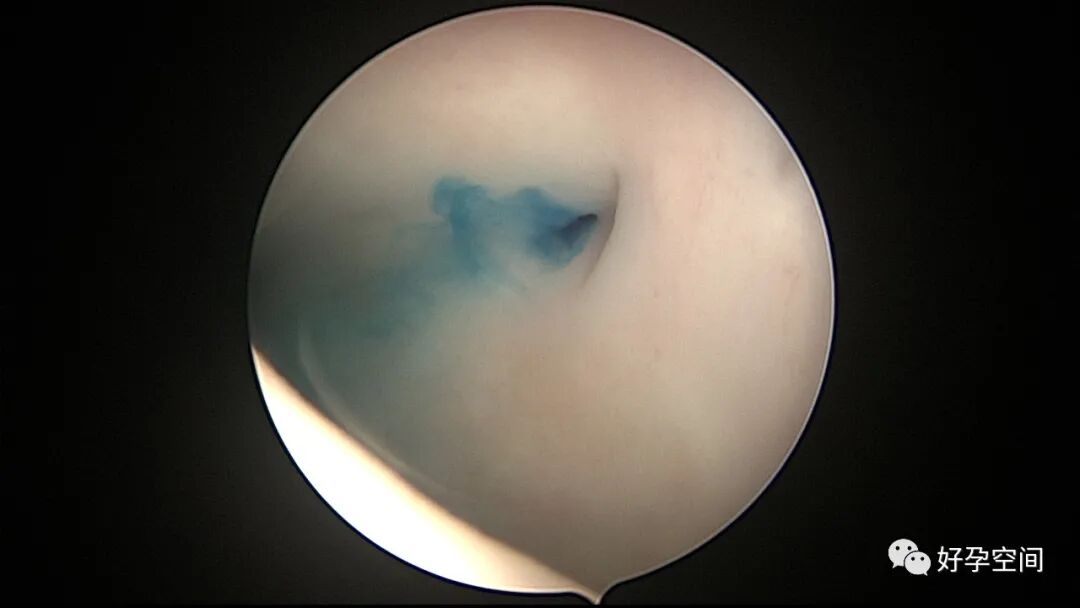

病例1:23岁,人流术后闭经半年,宫腔镜安装尿道切开钩形刀行宫腔冷切分粘,术后自然妊娠,足月分娩。